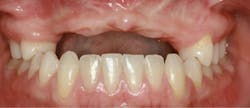

A 21-year-old female was injured five years ago in a jet ski accident. Seven of her maxillary teeth (Nos. 5–11) were avulsed along with the buccal plate. The patient was seen by several specialists to assess treatment options. Ultimately, she was allowed to heal over a few years (figure 1) and given a partial denture in the interim. The patient’s family had many consultations over the years to hear recommendations for restoring her smile with implant-retained crown-and-bridge treatment. At that point in time, options were expensive and the patient was too young to start treatment. The patient wanted fixed maxillary restorations to replace her missing teeth. Treatment began after the patient had graduated from high school and before entering college.

Figure 1: Full retracted view of full bite